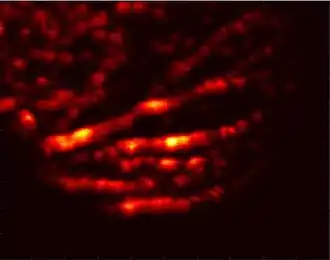

Visible light absorbers (λ = 400 to 700 nm) include oxyhemoglobin, deoxyhemoglobin, melanin, and cytochrome c. Visible light photoacoustic microscopy is particularly useful in determining hemoglobin concentration and oxygen saturation due to the difference in absorption profiles of oxyhemoglobin and deoxyhemoglobin. Real-time analysis can then be used to determine blood flow speed and oxygen metabolism rate.[3] In addition, photoacoustic microscopy is capable of early melanoma detection due to the high concentration of melanin found in skin cancer cells.

Photoacoustic microscopy has a wide range of applications in the biomedical field. Due to its ability to image a variety of molecules based on optical wavelength, photoacoustic microscopy can be used to gain functional information about the body noninvasively. Blood flow dynamics and oxygen metabolic rates can be measured and correlated to studies of atherosclerosis or tumor proliferation. Exogenous agents can be used to bind to cancerous tissue, enhancing image contrast and aiding in surgical removal. On the same note, photoacoustic microscopy is useful in early cancer diagnosis due to the difference in optical absorption properties compared to healthy tissue.[1]